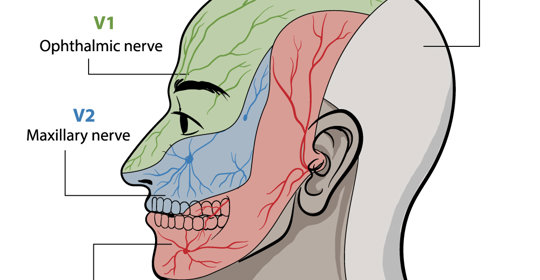

顱神經損害:三叉神經痛、第六腦神經麻痺